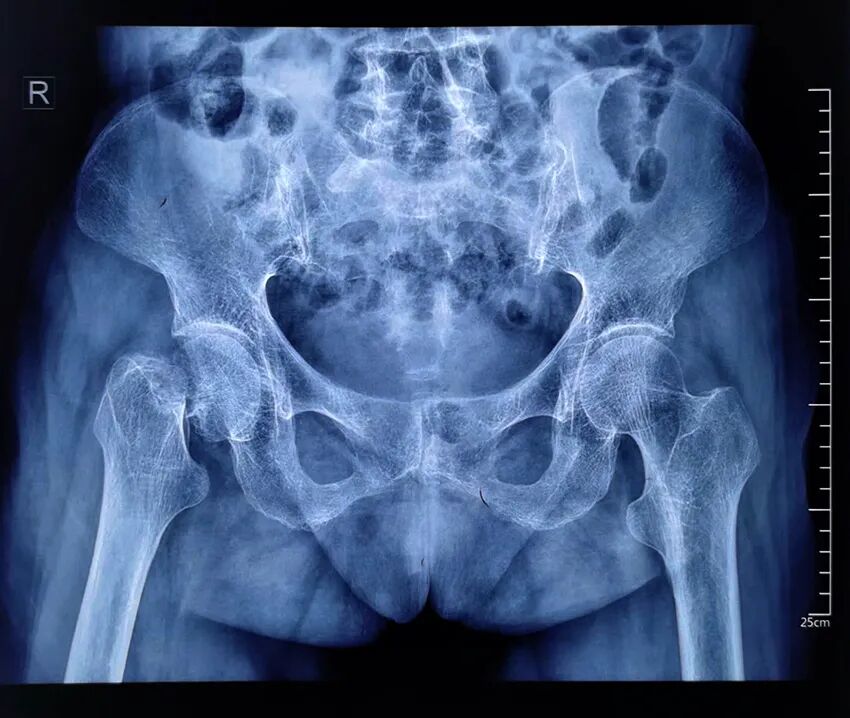

患者陈某,女性,身份证年龄102岁,实际年龄103岁,家住廉江横山镇某村。

入院:2022年10月8日;出院:2022年10月19日。

患者在家中不慎摔倒致右股骨颈骨折,不能站立及行走。家属送去多家医院都因年龄大,并发症多,拒绝接收,后通过朋友了解到到湛江骨科医院技术力量强、设备精良,多项骨科技术在粤西地区处于领先地位,特别是在老年髋部骨折手术治疗方面有丰富的经验,后慕名送到湛江骨科医院。

术前图像